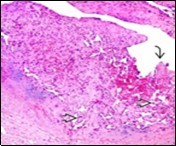

On microscopy, superficial squamous epithelial surface is intact. Sub-epithelial connective tissue stroma exhibits slit-like, vascular spaces. Upon extended magnification, multiple, intravascular papillary projections encompassed within a hyalinised stroma are discerned. Centroidal calcification appears in combination with intravascular, papillary endothelial cell proliferation, lined with singular layer of endothelial cells devoid of cytological atypia6, 7.

Characteristically, the vascular neoplasm denominates numerous papillae within blood vessels. Papillae are coated with singular or dual layer of flattened endothelial cells with an encompassing hyalinised, fibrous tissue core. Vascular lumen is distended with thrombosis. Foci of haemorrhage with fibrinous and purulent exudate are discerned. Tumour perimeter depicts inflammatory granulation tissue. Cholesterol clefts and focal reactive bone formation may concur. Extraneous squamous epithelium may be discontinuous and ulcerated. The neoplasm is devoid of features of malignancy4, 6.

Numerous micro-calcifications can be observed within the lesion which may engender vascular occlusion and tissue necrosis6. Figure 1, Figure 2, Figure 3, Figure 4, Figure 5, Figure 6, Figure 7, Figure 8.

Figure 4.Papillary endothelial hyperplasia enunciating papillary arrangements coated with single layer of endothelial cells intermingled with significant fibrinous and thrombotic exudate13.